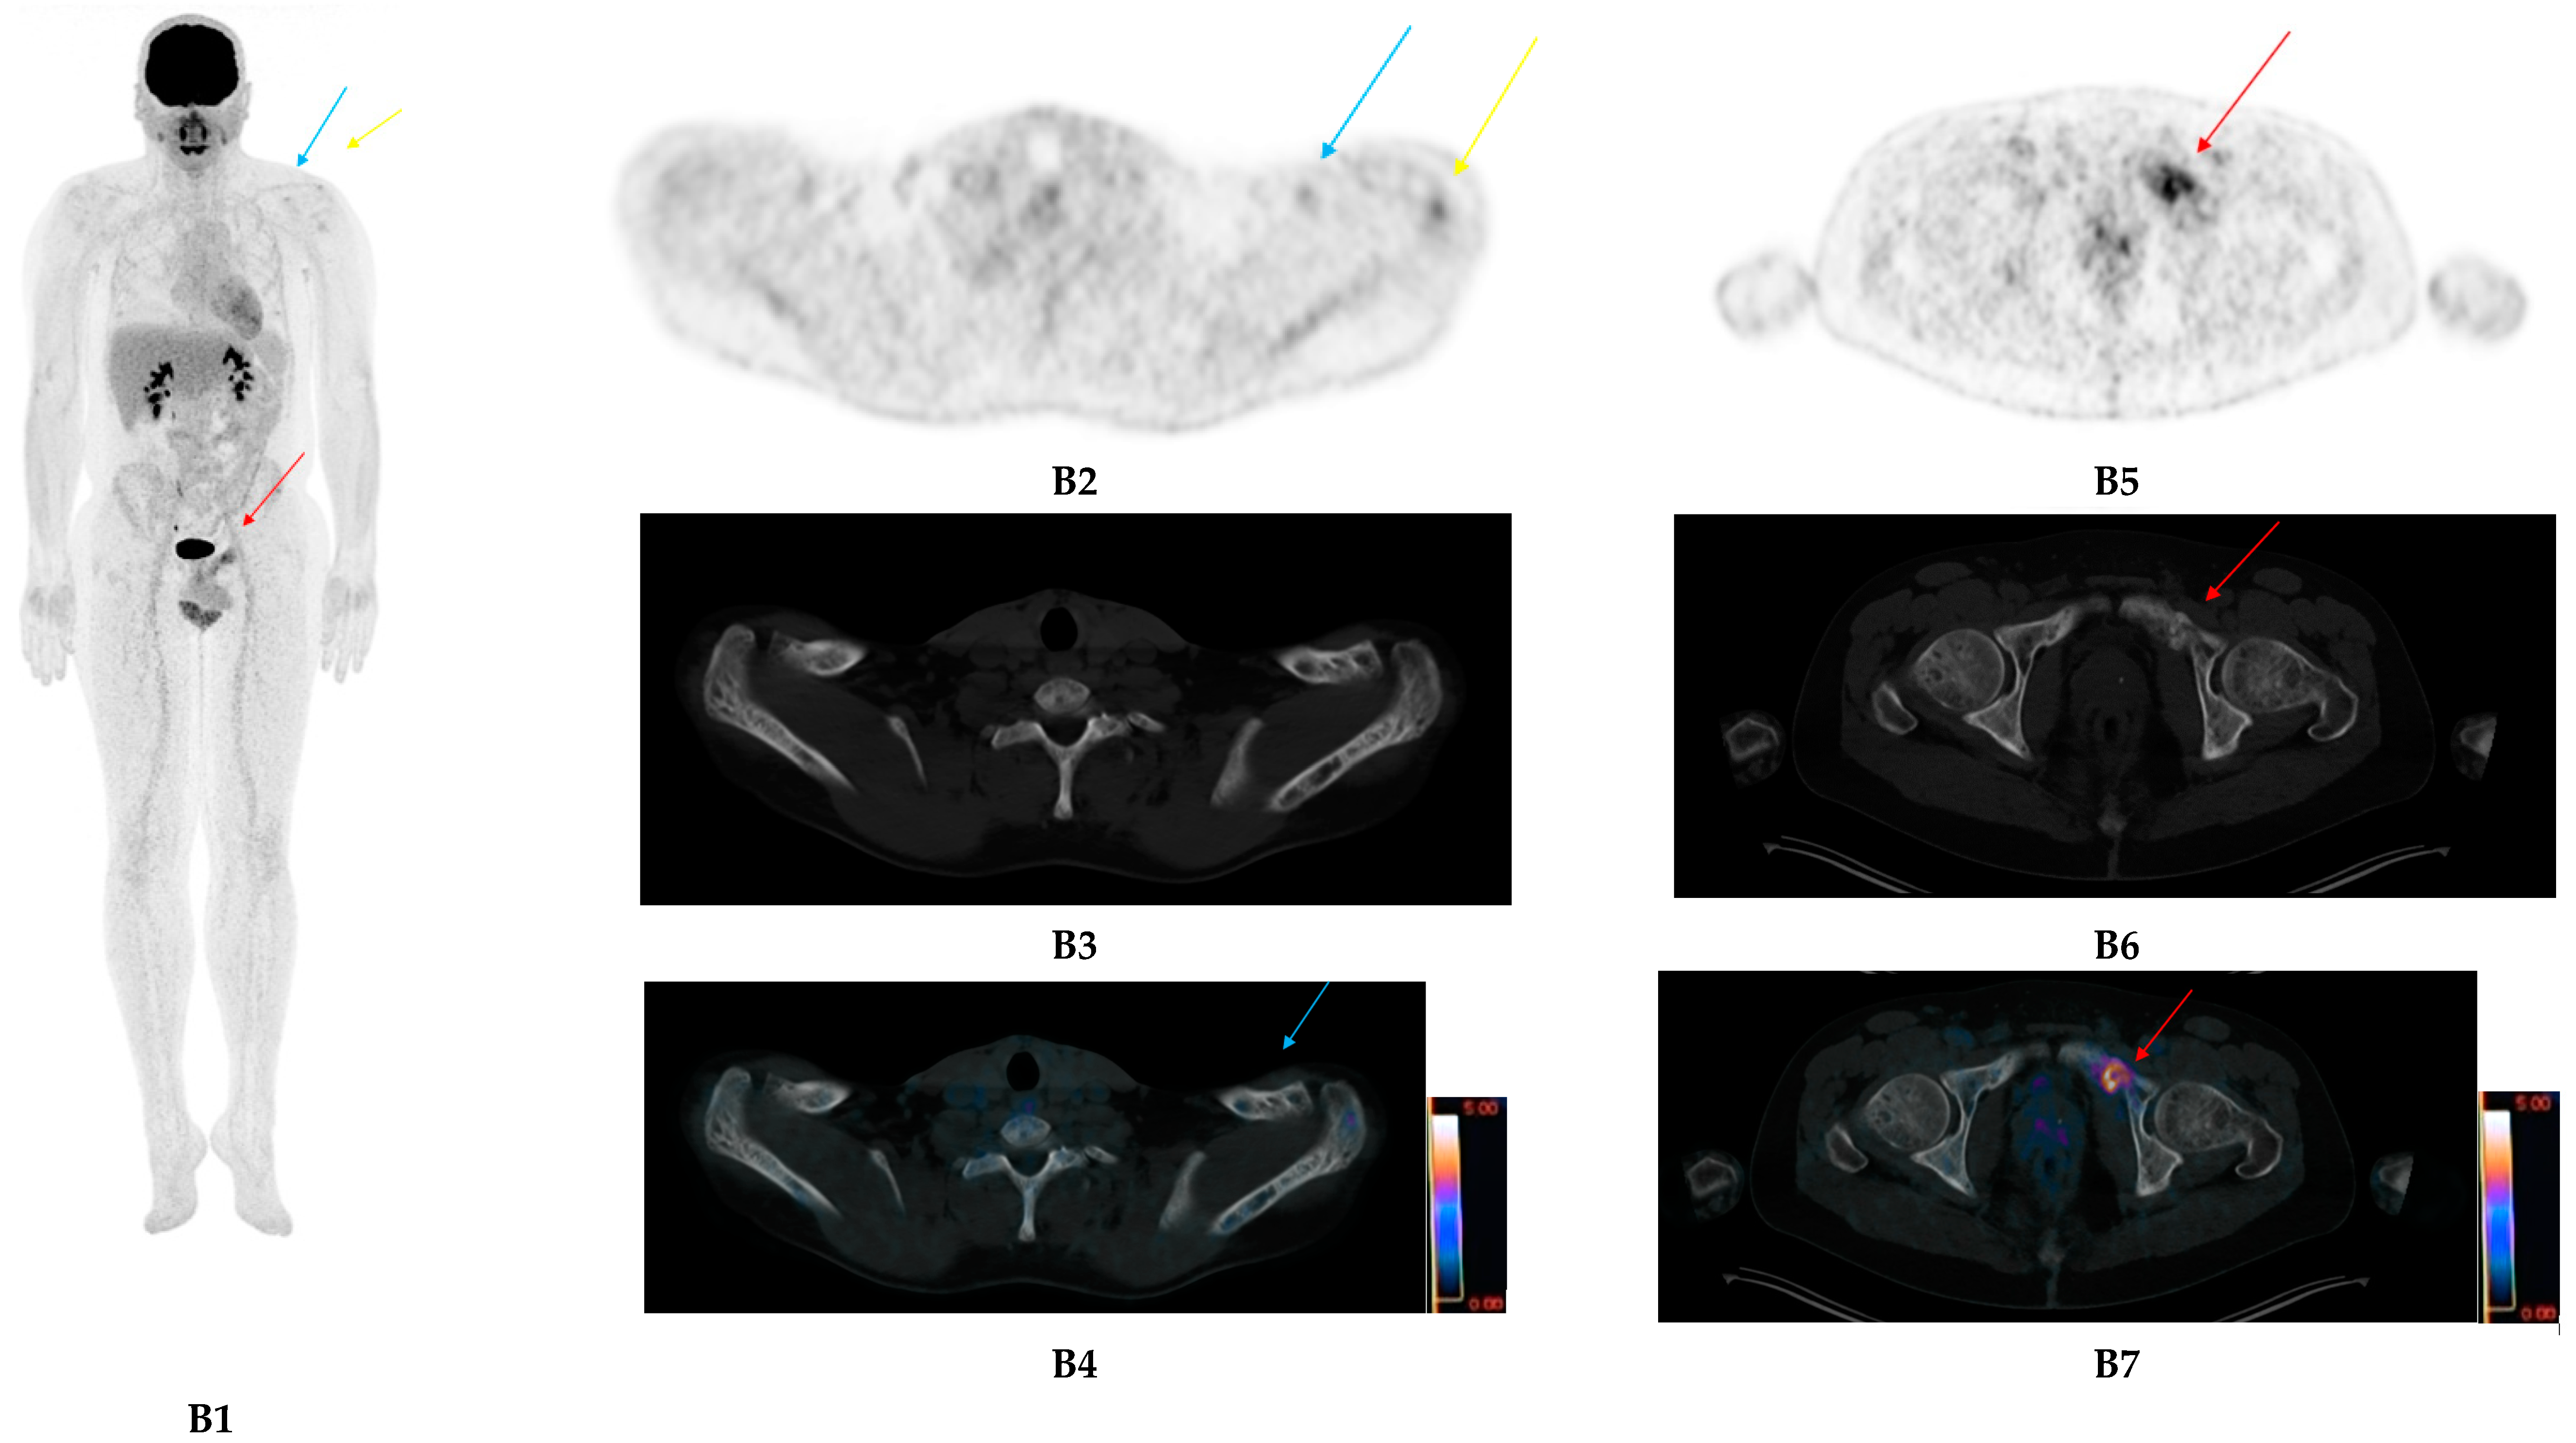

- Pan, Q.; Cao, X.; Luo, Y.; Li, J.; Feng, J.; Li, F. Chemokine receptor-4 targeted PET/CT with 68Ga-Pentixafor in assessment of newly diagnosed multiple myeloma: Comparison to 18F-FDG PET/CT. Eur. J. Nucl. Med. Mol. Imaging 2019, 47, 537–546. [Google Scholar] [CrossRef]